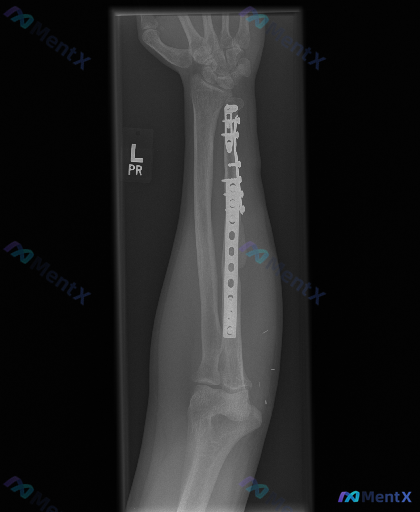

各位同道,今天我们来讨论一张左侧前臂的正位X光片。这是一位尺骨远端陈旧性骨折术后的患者复查片。请大家先看看这张片子,说说你观察到了什么异常?接下来我们会结合片子展开分析。